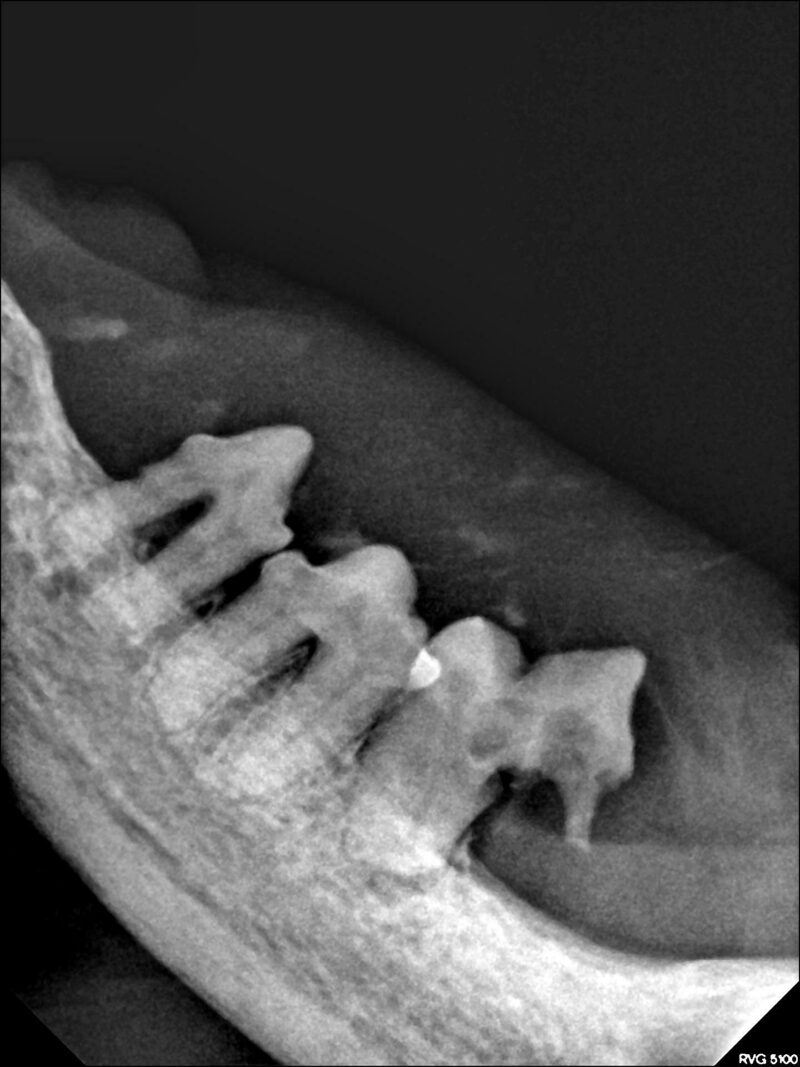

Die tägliche Erfahrung hilft uns dann, die richtigen Entscheidungen zu treffen. Zweifelsohne ist bei der Katze die komplette Dentalröntgenuntersuchung unverzichtbarer Teil einer fundierten Diagnosestellung geworden.

Ein Zahn mit einem grenzwertigen Befund wird beim geriatrischen Patienten möglicherweise eher gezogen als erhalten. Andererseits wird man sich beim älteren und beim Risikopatienten für eine möglichst unkomplizierte Vorgehensweise entscheiden. Sehr umfangreiche Operationen sollten im Interesse des Patienten möglicherweise auf mehrere Termine aufgeteilt werden. Somit ist ein besonderes Augenmerk auf ein gutes Zeitmanagement zu richten.